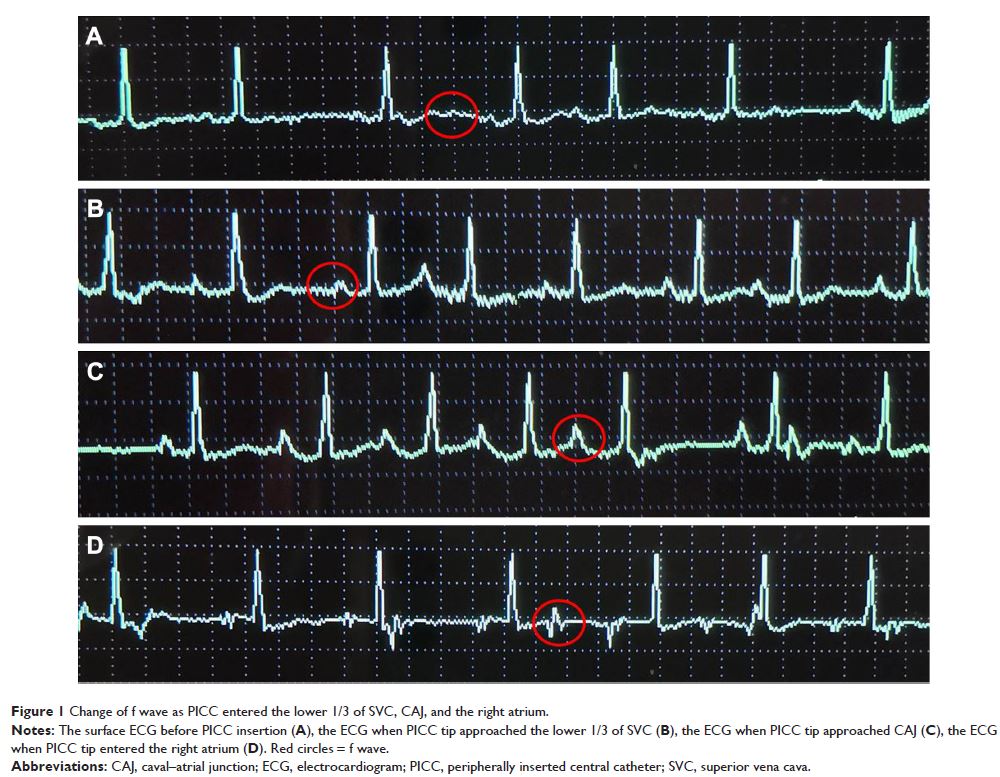

- 作者:Wei Wu, Dong-Xia Li, Qing Wang, Ying Xu, Yun-Jing Cui

- 期刊:Clinical Interventions in Aging